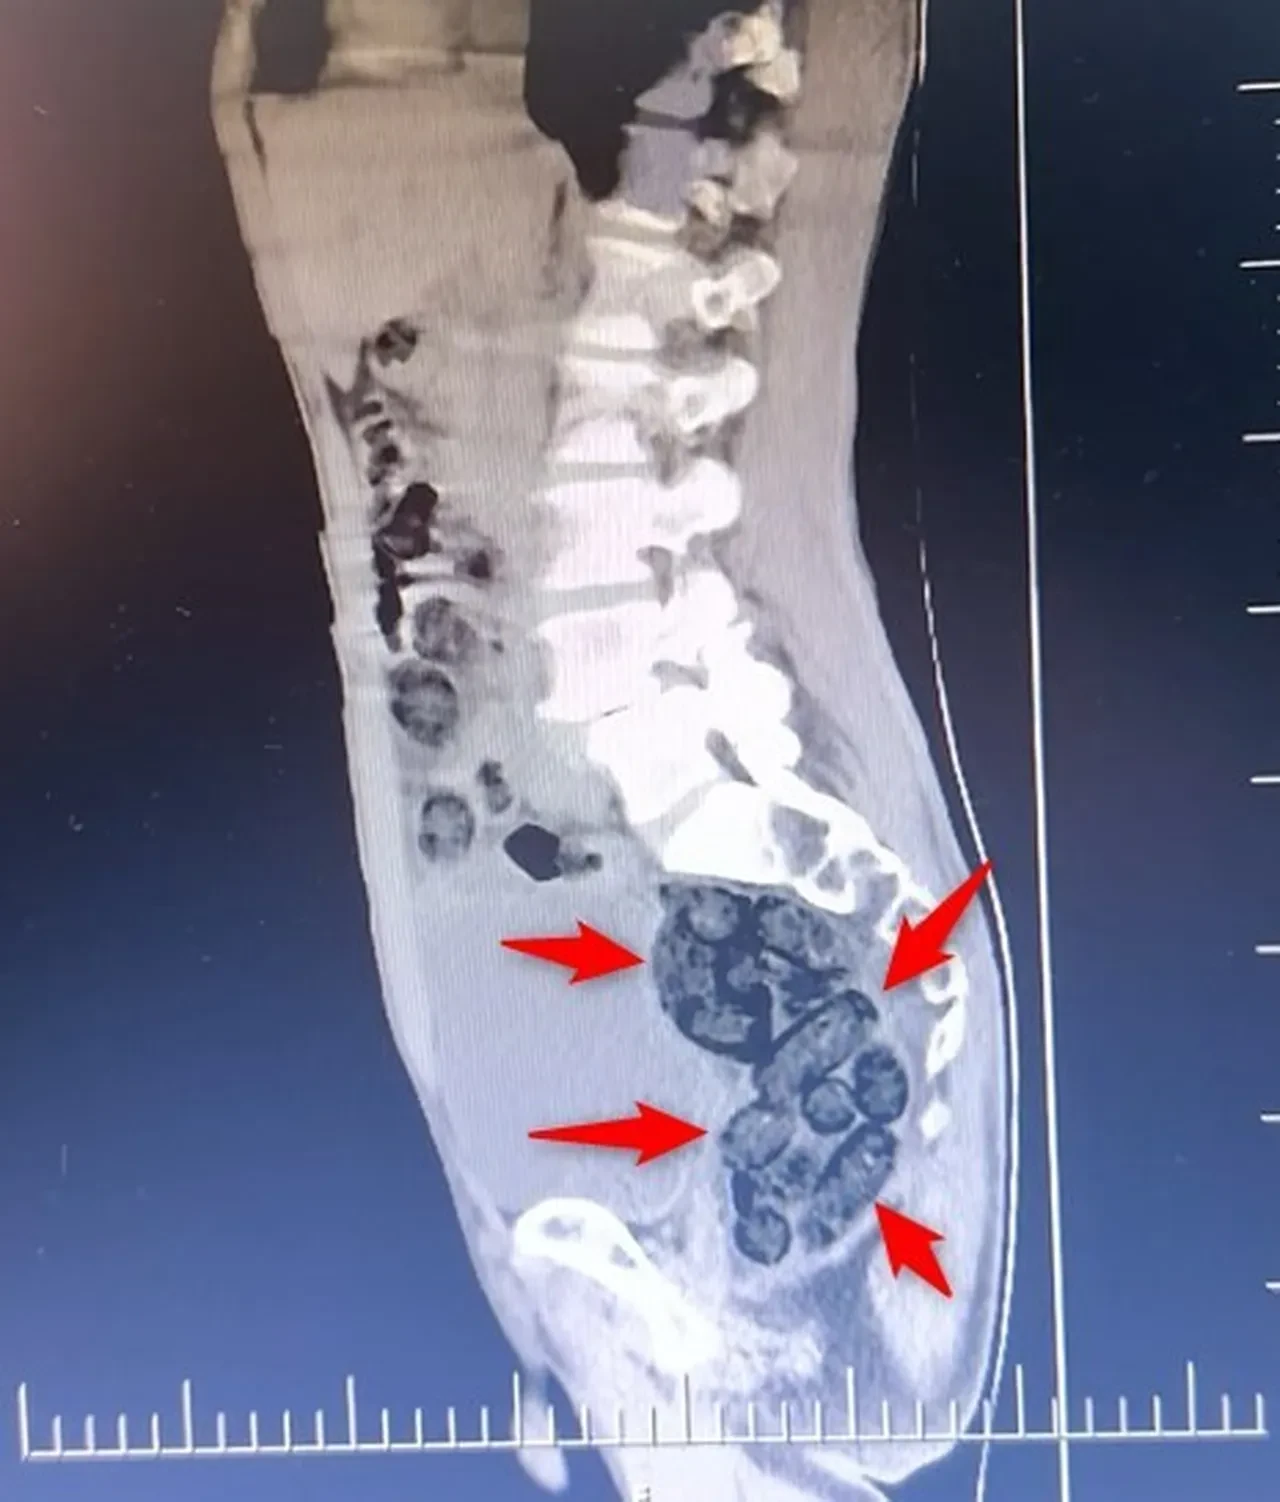

Yapılan incelemeler sonucunda yabancı uyruklu şahsın midesinde 64 Parça halinde toplam 472 gram uyuşturucu maddesi metamfetamin olduğu belirlendi. Gözaltına alınan şahsın midesindeki uyuşturucu madde çıkartıldı. Emniyetteki işlemlerinin ardından adliye sevk edilen şahıs, çıkarıldığı mahkemece tutuklanarak cezaevine gönderildi.